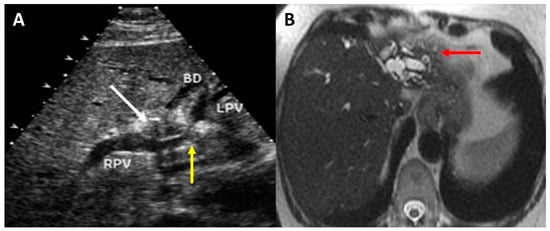

2. Preoperative Imaging